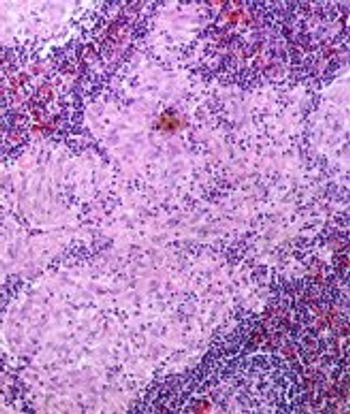

High-risk HPVs may be present more frequently than previously estimated in a variety of head and neck cancers, supporting the use of a combination of methods to detect high-risk strains.

A small retrospective study has identified several biomarkers that were significantly altered in patients with head and neck squamous cell carcinoma. If further validated, these serum biomarkers could facilitate early diagnosis.

Researchers have identified several risk factors that may help predict which patients with oropharyngeal cancer may require a percutaneous endoscopic gastrostomy tube during chemoradiotherapy, according to a newly published review.

Black race did not adversely affect outcomes after receiving radiotherapy for head and neck squamous cell carcinoma compared with white race, according to the results of a study in which black patients made up the majority of enrolled participants.